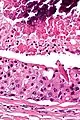

Their histologic appearance is similar to ductal breast carcinoma.

Very high mag.